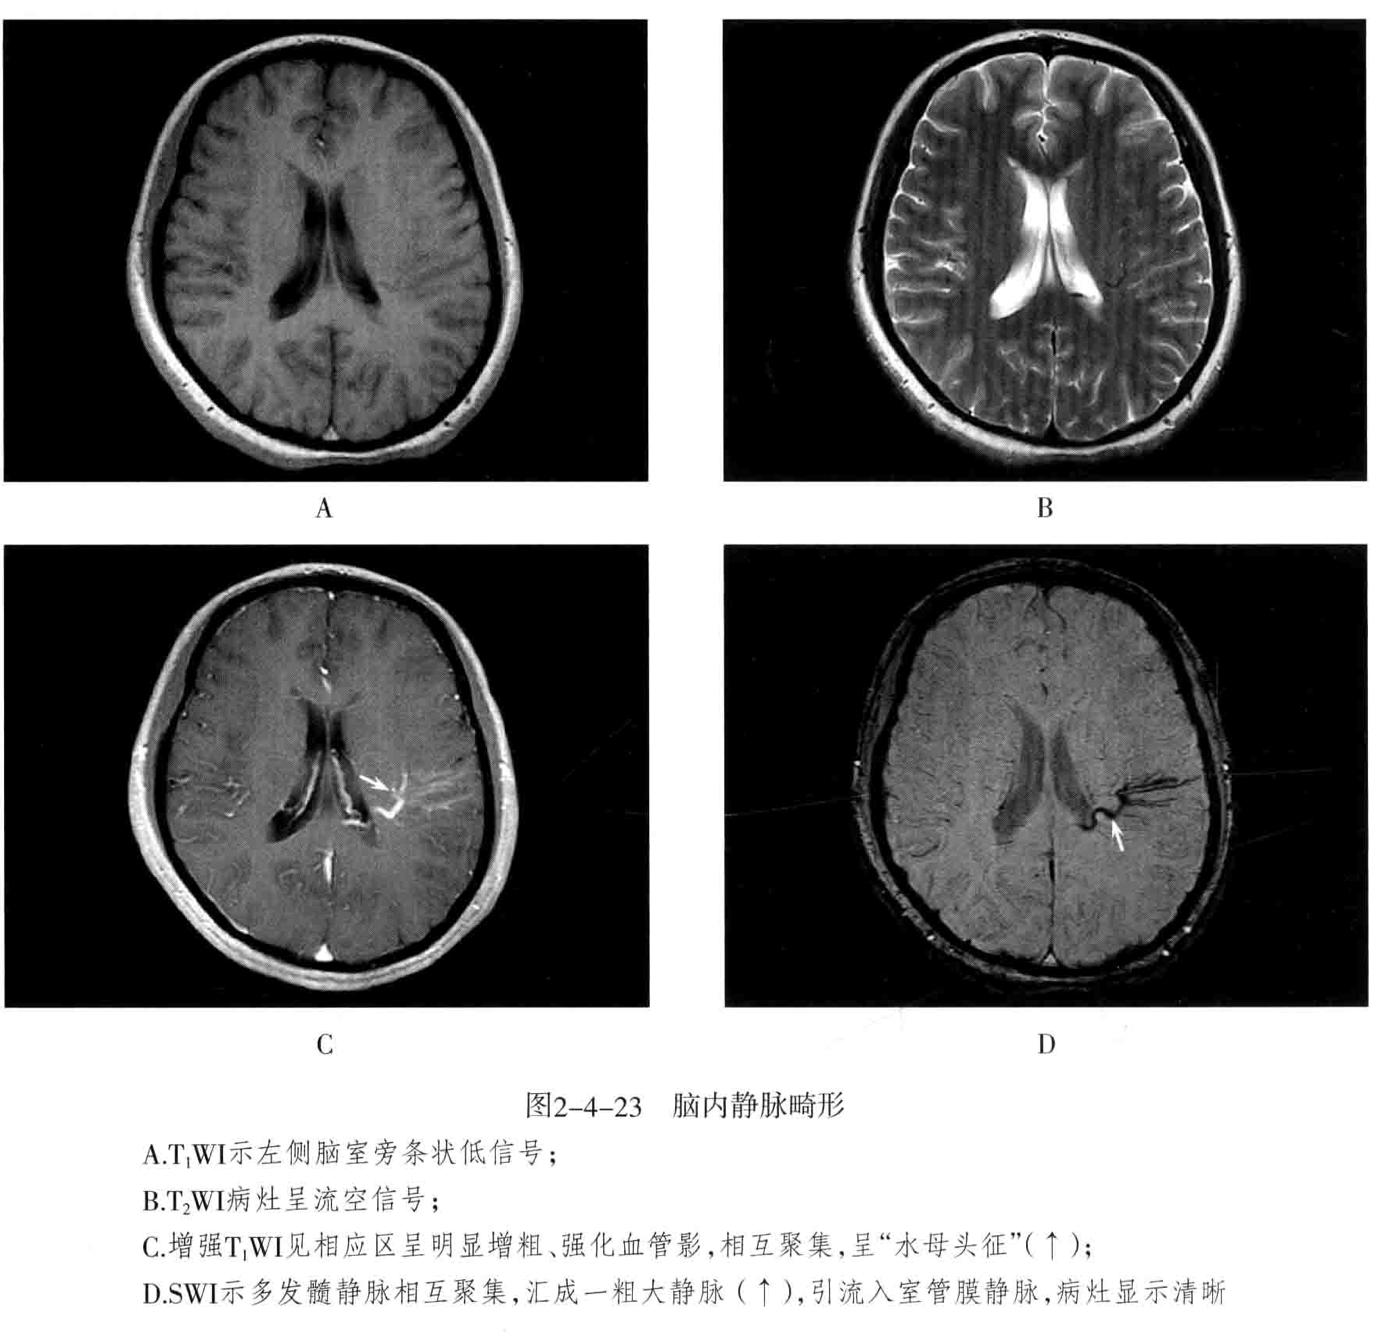

• 静脉畸形 主要包 静脉性血管瘤 大脑大静脉畸 形(Galen静脉瘤)

1. 脑静脉性血管瘤 极为少见。静脉性血管瘤是一种组织上完全由静脉成分构成的脑血管畸形,任何年龄均可见,病理特点为许多放射状排列的扩张髓静脉连接成一条或多条扩张的经皮质或室管膜下引流静脉,最后汇入静脉窦。常发生于 额叶及小脑,以第四脑室周围多见 ,常伴发其他血管畸形,最常见为海绵状血管瘤。

2. CT表现:平扫显示不清,周围无脑水肿,有时可见出血等改变,CTA典型表现为额叶或小脑许多细小髓静脉放射状汇入一条或几条引流静脉,最后汇入静脉窦,呈“水母头征”。

3. MRI表现:可因病灶大小及血流速度不同而在MRI上呈多种信号,T1WI、T2WI多呈流空信号,少数由于血流缓慢也可呈略高信号,FLAIR呈低信号。增强后髓静脉及引流静脉明显强化,典型者呈“水母头征”,引流静脉可走向脑表面而引流至静脉窦,或走向脑室引流至室管膜静脉。MRV可显示引流静脉及其引流情况,但不显示髓静脉,SWI序列对本病显示很敏感。病灶周围无脑水肿表现,有时可见出血。

4. 鉴别诊断:动静脉畸形:由供血动脉、畸形血管团、粗大引流静脉构成。海绵状血管瘤:多可见不同时期反复出血的产物,周围脑实质多有脑萎缩改变,MRI呈爆米花样改变为特征,周边见含铁血黄素环,增强后轻度或无去强化。